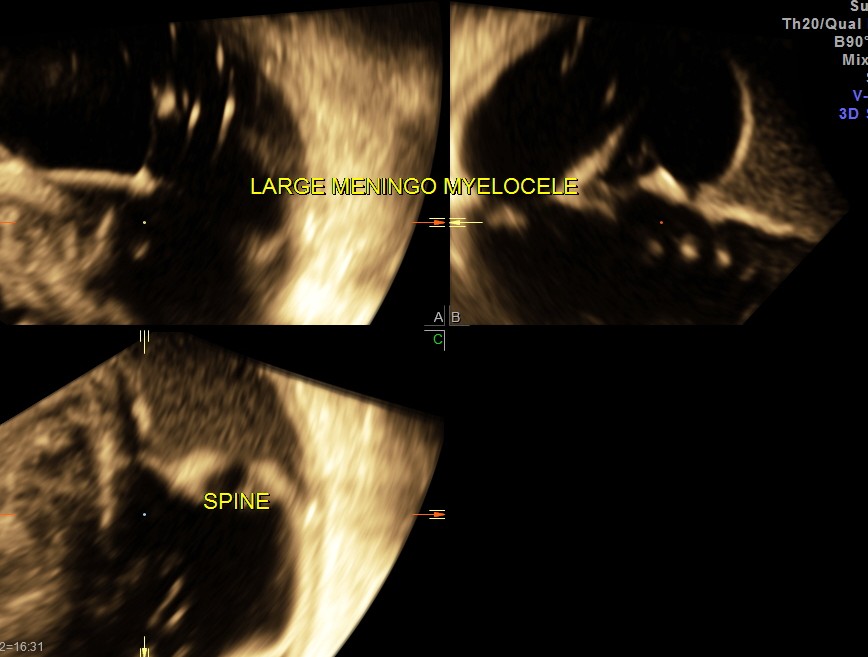

This was a 22 year old primi gravida , sent for scan at 36 to 37 weeks of gestation.

She had undergone 2 scans at government hospital and another scan at a private clinic at 16 , 22 and 28 weeks of gestation.Now she was referred as the sonologist at a different centre suspected a lesion.

The following are the images .

This was a sad finding at 37 weeks of gestation and should have been detected earlier.